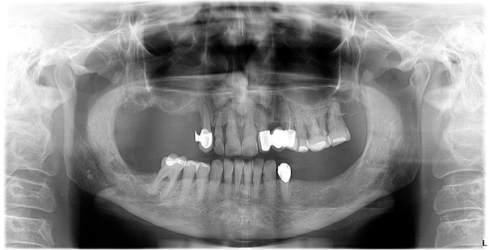

Prije početka bilo kakvih radova u ustima potrebno je napraviti ortopan snimku da bi se uočile eventualne upale na zubu, neadekvatni endodontski zahvati ili upale zubnog mesa. Nakon sanacije takvih nedostataka zubi se bruse i uzimaju se otisci.

Implantologija je grana dentalne medicine koja objedinjuje znanja i vještine iz više područja opće i dentalne medicine, poglavito anatomije, oralne kirurgije, parodontologije i protetike.

Dentalni implantat je vijak izrađen od titana koji se operacijski ugrađuje u kost. Da bi se potpuno nadoknadio gubitak zuba osim implantata potrebni su još protetska nadogradnja te protetska krunica. Tek tada imate u ustima zub koji nedostaje. Implantati glume korijen zuba i u ustima nisu vidljivi, dok zubne krunice i proteze predstavljaju suprastrukturu (vidljivi dio) koja se preko različitih metoda vežu sa implantatom i tako čine cjelinu.

U današnje vrijeme implantat je najsuvremeniji način rješavanja bezubosti, od nedostatka jednog zuba pa sve do potpuno bezubih čeljusti. Dakle implantatom se može nadoknaditi jedan zub ili nekoliko zubi pa tada govorimo o mostu na implantatima. Također danas je jako popularno nadoknaditi sve zube u potpuno bezuboj čeljusti sa 4 ili 6 implantata i mostovima na njima (tzv All on 6 ili All on 4).

1. Pregled pacijenta i CBCT snimanje

Bilo da je pacijent došao samoinicijativno sa željom za ugradnjom implantata ili smo mu mi to sugerirali, važno je obaviti razgovor u kojem poslušamo pacijentove želje i motive, ali i mi objasnimo mogućnosti rekonstrukcije kao i način na koji se izvodi operacija. Važno je uzeti anamnezu, te saznati opće zdravstveno stanje pacijenta. Kad dogovorimo i uskladimo sve navedeno pacijenta šaljemo na CBCT snimanje. CBCT snimanje vrlo je bitno u planiranju implantološke terapije, budući da takva snimka omogućuje prikaz u tri dimenzije, neophodan za stručno i kvalitetno planiranje terapije. CBCT snimka se unosi u BTI program koji nam pokazuje sve anatomske strukture, visinu i širinu kosti, te mjeri gustoću, odnosno kvalitetu kosti. Isti program omogućuje nam određivanje najboljih dimenzija i najboljeg položaja budućih implantata.